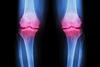

NewsInjectable gel targets osteoarthritis pain

Hydrocelin shows promising preclinical results in treating osteoarthritis, offering pain relief and potential joint protection with no observed side effects.

NewsCombatting osteoarthritis with cartilage replacement therapy

Limb bud progenitor cells efficiently generated new cartilage in osteoarthritis patients, which could lead to cartilage replacement therapy.